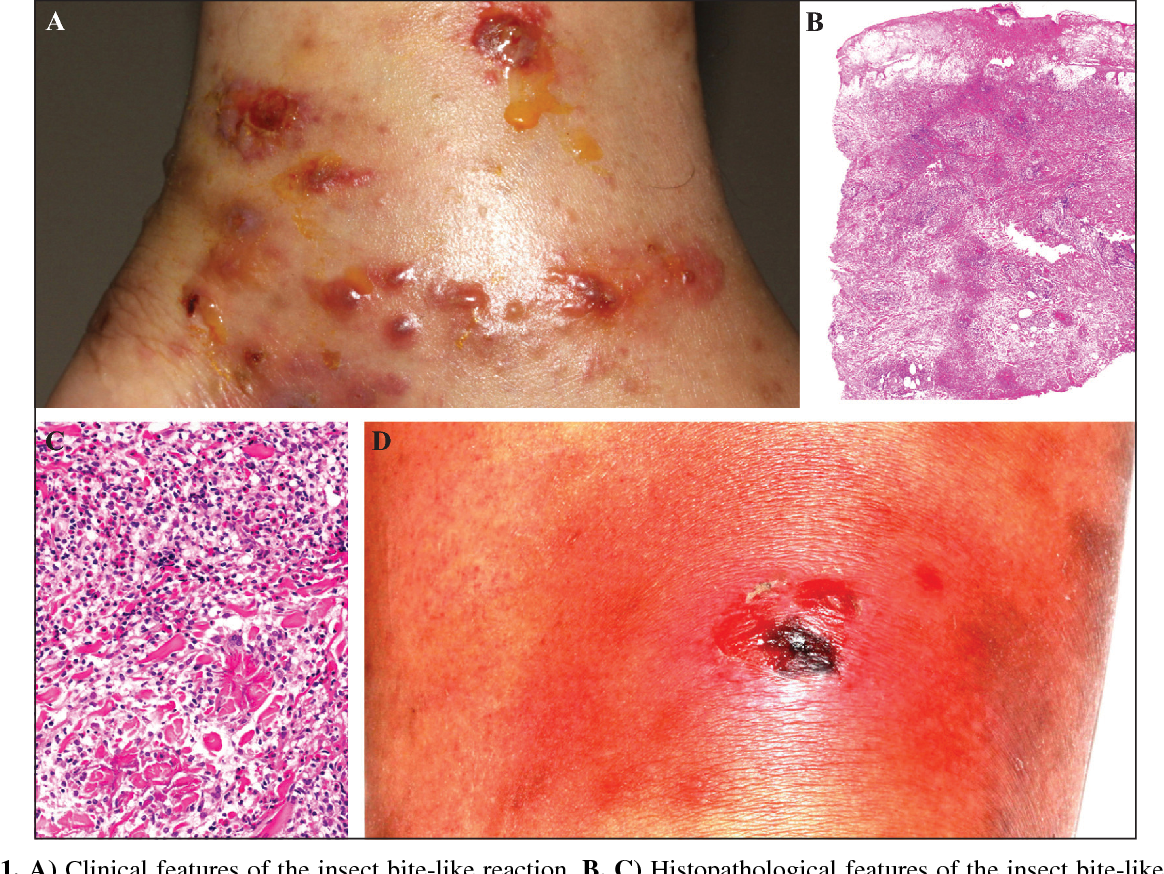

![Eosinophilic Cellulitis PDF] Flame figures associated with eosinophilic dermatosis of hematologic malignancy: is it possible to distinguish the condition from eosinophilic cellulitis in patients with hematoproliferative disease? | Semantic Scholar, image size:1200x672](https://figures.semanticscholar.org/6493287009fa9c164615e725d82a8c7c663c00b5/2-Figure1-1.png)

PDF] Flame figures associated with eosinophilic dermatosis of hematologic malignancy: is it possible to distinguish the condition from eosinophilic cellulitis in patients with hematoproliferative disease? | Semantic Scholar

Eosinophilic cellulitis (Wells' syndrome) and an insect bite-like reaction in a patient with non-Hodgkin B cell lymphoma. | Semantic Scholar